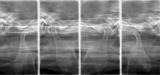

Radiografia Panorâmica (Fig. 1) fornece informações do Complexo Dento-Maxilo-Facial e a Radiografia específica (Fig. 2) da Articulação Temporandibular (Posições: Boca Aberta e Boca Fechada) temos a imagem das posições da movimentações do Côndilo

A Radiografia sinaliza para as avaliações das Estruturas Ósseas (Fig. 1) e com detalhes da ATM (Articulação Temporomandibular (Fig. 2).